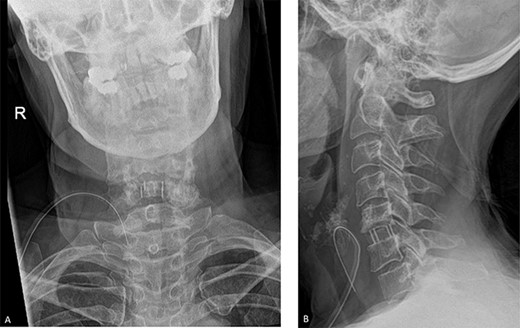

She was further referred for spinal magnetic resonance imaging (MRI) which revealed a C5–C6 disc compression (Fig. 1). Following the scan, she was further referred to neurosurgery where a discussion was carried out with regards to the risks and benefits of surgery to relieve the pressure on the nerves. Given the thecal compression and the significant pruritus refractory to any therapy, the decision was to proceed with a surgical intervention.

MRI showing bilateral C6 nerve root compression and left C7 nerve compression, C5–C8 disc herniation indenting the ventral aspect of the cord without typical signs of compression myelopathy or significant intramedullary signal abnormality. A. Sagittal view. B. Axial view.